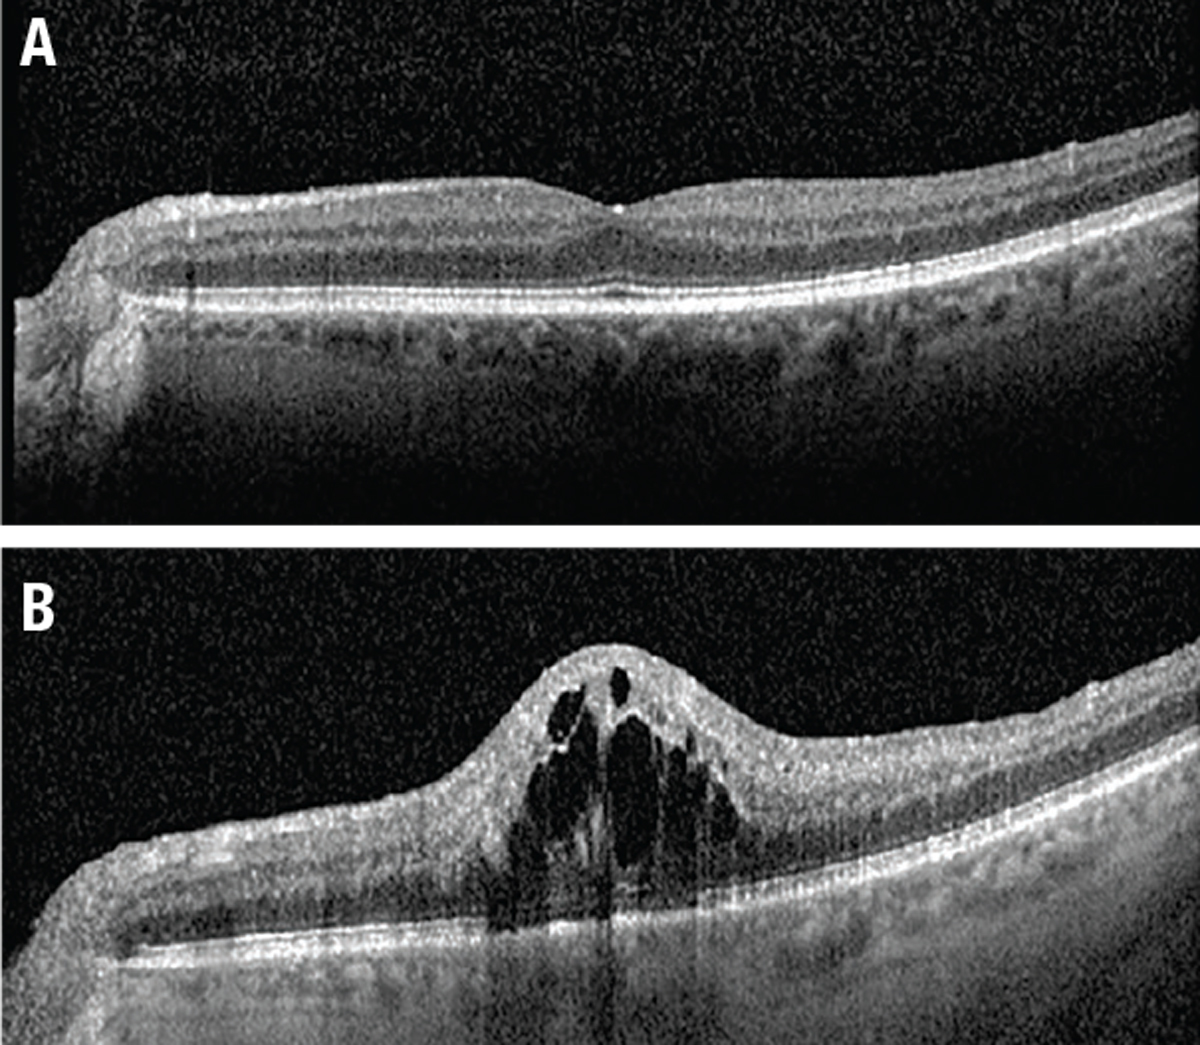

![]() |

| Figure 3. A) Optical coherence tomography at presentation shows no macular edema. B) Five weeks later, OCT shows diffuse central cystic intraretinal fluid. |

Three weeks later, and five weeks after his initial presentation, the patient returned with reduced VA of 20/60 and new macular edema on OCT. We treated him with intravitreal bevacizumab.